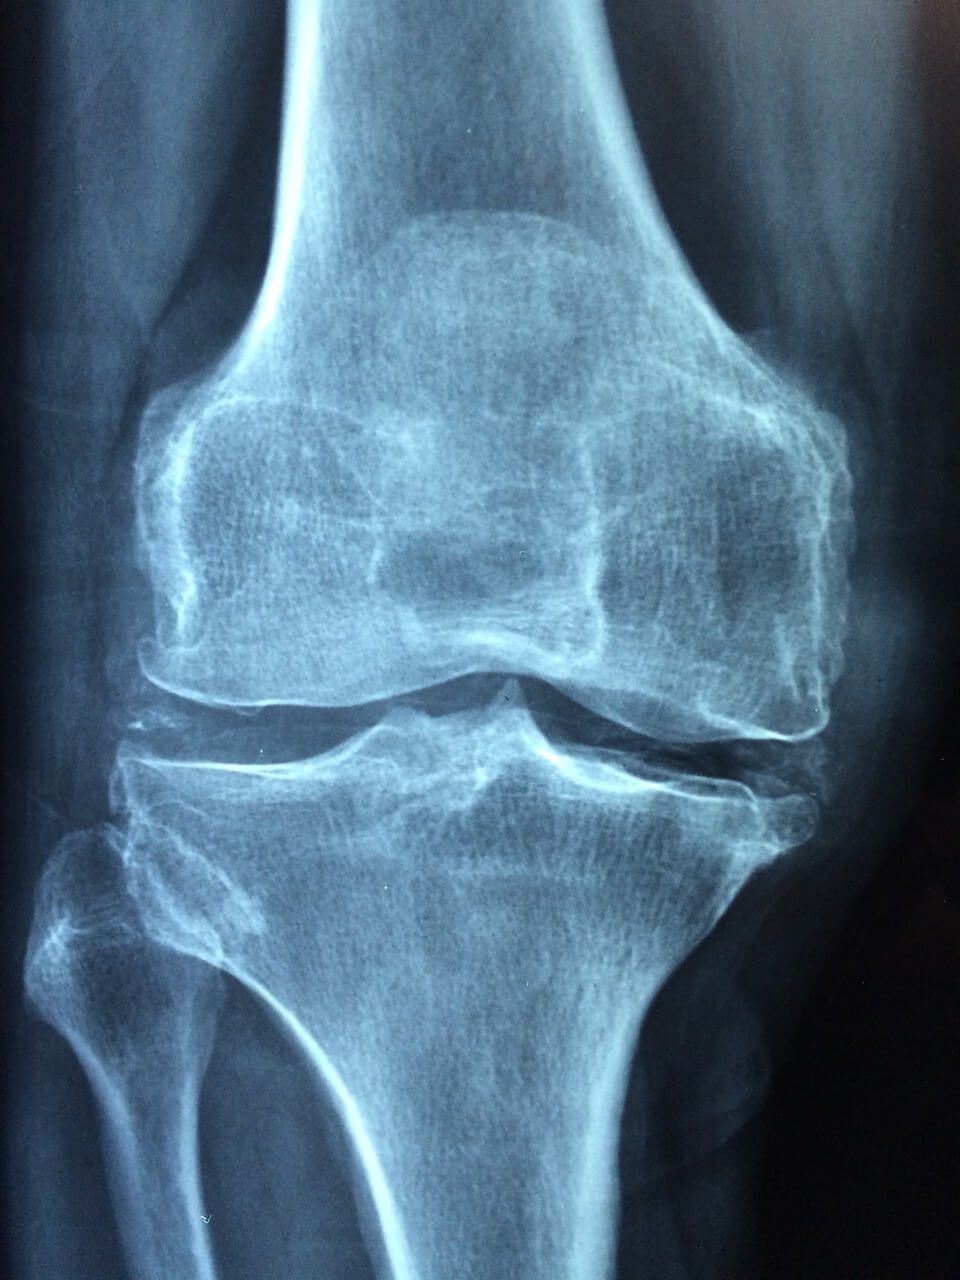

관절 건강을 지원하는 영양제는 다양하게 시장에 나와 있습니다. 그 중에서도 글루코사민과 콘드로이틴은 관절 연골의 건강을 보호하고 염증을 줄이는 데 도움을 줄 수 있습니다. 또한 오메가-3 지방산은 관절 염증을 감소시키고 유연성을 증진시키는 데 도움이 됩니다. 관절 영양은 평소에 관리하는 것이 중요하며, 나이가 들수록 쉽게 회복되기 어려운 관절과 관련된 사안은 반드시 가볍게 여기지 않아야 합니다.

관절 영양제 추천 30대가 넘는 성인이거나 60대가 넘으셨다면 관절 영양제 복용을 통해 얼마든지 건강한 관절을 유지하며 삶을 즐기실 수 있습니다. 더불어 올바른 식습관과 꾸준한 운동, 적절한 관절 영양제 복용은 풍요로운 노후를 위한 중요한 요소입니다. 지금 관절 상태를 점검해보시고, 관절 가동성 또는 통증 등 문제가 있다면 지체없이 가까운 병원을 내방하셔서 상담받아보시기 바랍니다.